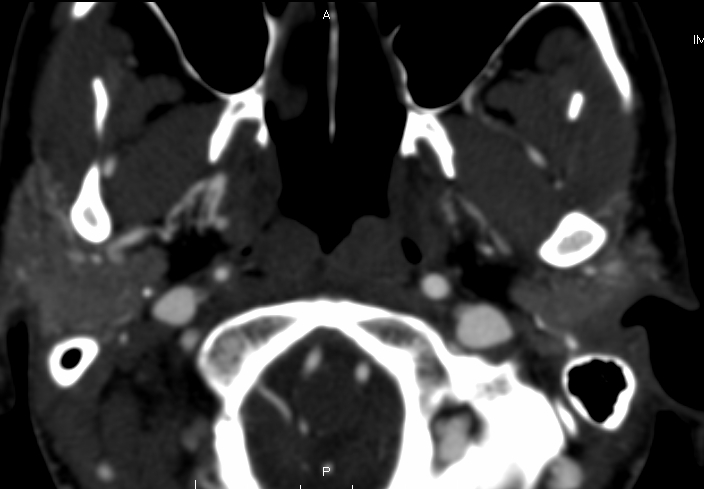

Better imaging for carotid dissection is contrast enhanced CT angiography or MR angiography. The classic sign of dissection on CT or MR is of called a flare. A flare is the narrowed lumen. It looks like a narrow flame. Other findings are the dissection flap or a contrast filled crescent. Sometimes a pseudoaneurysm is visible.

Here is an example. This is a CT of the same patient as the beginning of this article. This CT was performed 3 months later than the other one. Notice there is better flow in the right carotid artery. This points to a healing process of the dissection: